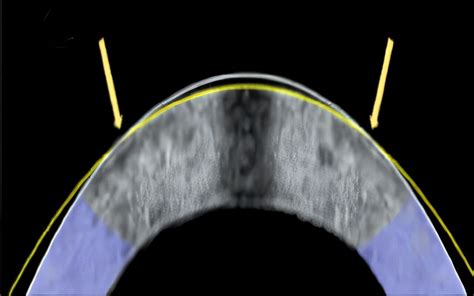

This step is often the most unique aspect of what is Lasik eye surgery. The surgeon creates a thin, hinged flap on the surface of the cornea. This flap provides access to the underlying corneal tissue that needs reshaping.

Modern LASIK typically uses a femtosecond laser to create this flap with incredible precision. Once the flap is created, the surgeon carefully folds it back, like turning the page of a book, revealing the middle layer of the cornea (the stroma).